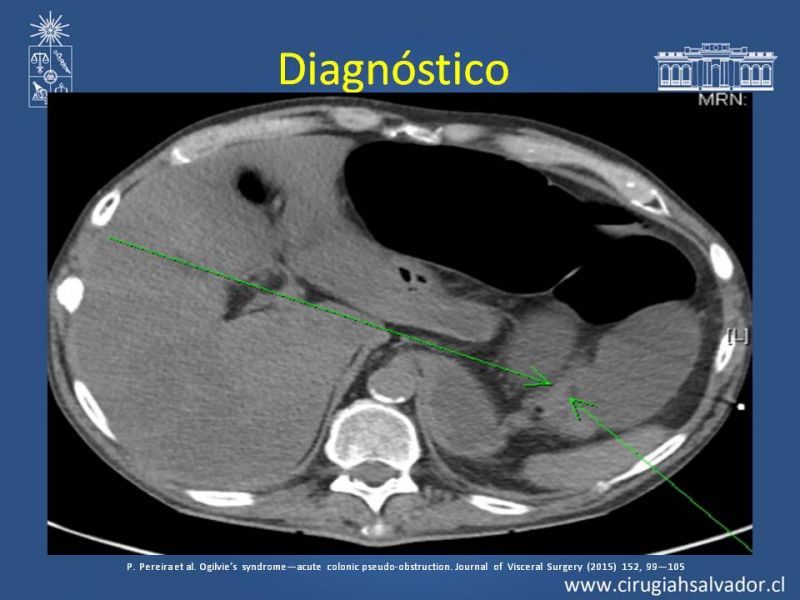

Sd Ogilvie

Coloproctología

| Autor: Dr. Roberto Olguín